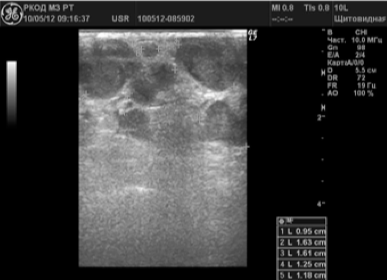

In 127 (83,6%) pacienți în timpul suspectate leziuni maligne ganglionii limfatiche-parametru au fost identificate cu ultrasunete. În 69 (45,4%) cazuri de limfom malign suspectate. Vizualiza mai multe noduri limfatici periferice mai multe zone, dintre care multe au fost lipite împreună (Fig. 2).

Ganglionii limfatici ai gâtului cu Chlamydia

Prevalau noduri formă rotunjită, P / PP<2,0 (84%). Большин-ство ЛУ (89,9%) были гипоэхогенными с гетерогенными внутренними эхосигналами, область ворот либо не дифференцировалась, либо была резко сужена. В допплеровских режимах в пораженных ЛУ определялся усиленный смешанный тип крово-тока с повышенной перфузией как в центре, так и по периферии ЛУ в 82,6% случаев.